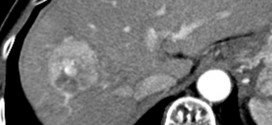

El hepatoma. Tumor maligno en general y especialmente el formado por células epiteliales, a saber. El hígado está situado en la parte superior derecha de la cavidad abdominal, debajo del diafragma y por encima del estómago, el riñón derecho y los intestinos. El hígado tiene forma cónica, es de color marrón rojizo oscuro y pesa alrededor de 3 libras. El …